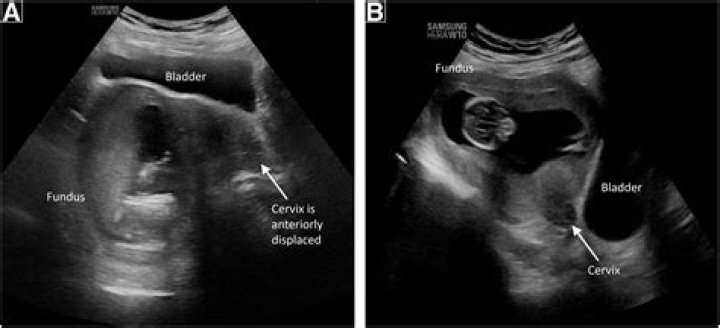

Having a tilted uterus (also called an inverted uterus, tilted cervix, or retroverted uterus) is perfectly normal. It just means that your uterus is tilted backward toward your spine rather than forward. A retroverted uterus has no effect on your ability to get pregnant.

The positioning of the uterus can change from anteversion to retroversion due to the filling of bladder or during pregnancy; however, changing from retroverted to anteverted position without prior pregnancy or endometriosis is rather uncommon.